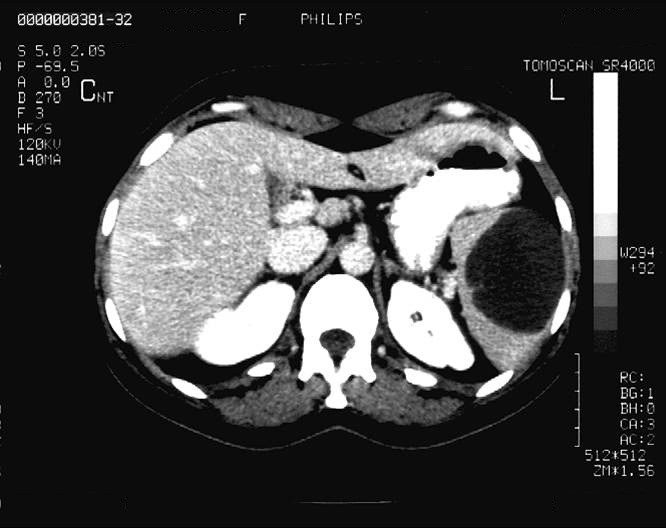

14.1.1.3. CT

Nowadays, CT is a basically important method amongst the modern diagnostic imaging services. (Figure 4) By the application of the multidetector CTs a chance is given to perform multiphase (without contrast, arterial, portal and late phase) CT scans, which provide important additional information because of the different hemodynamics of certain intrahepatic nodules. Multiplanar (sagittal, coronal, oblique) and 3D reconstructions can be adopted from the axial plane CT slices. Due to CT angiographic techniques, excellent spatial resolutional 3D reconstructional images can be performed both on the arterial (hepatic artery) and the venous sides (portal vein, hepatic veins, collateral veins in case of portal hypertension, CT control of transjugular portosystemic shunts)..

Figure 4. Liver, contrast enhanced CT, venous phase